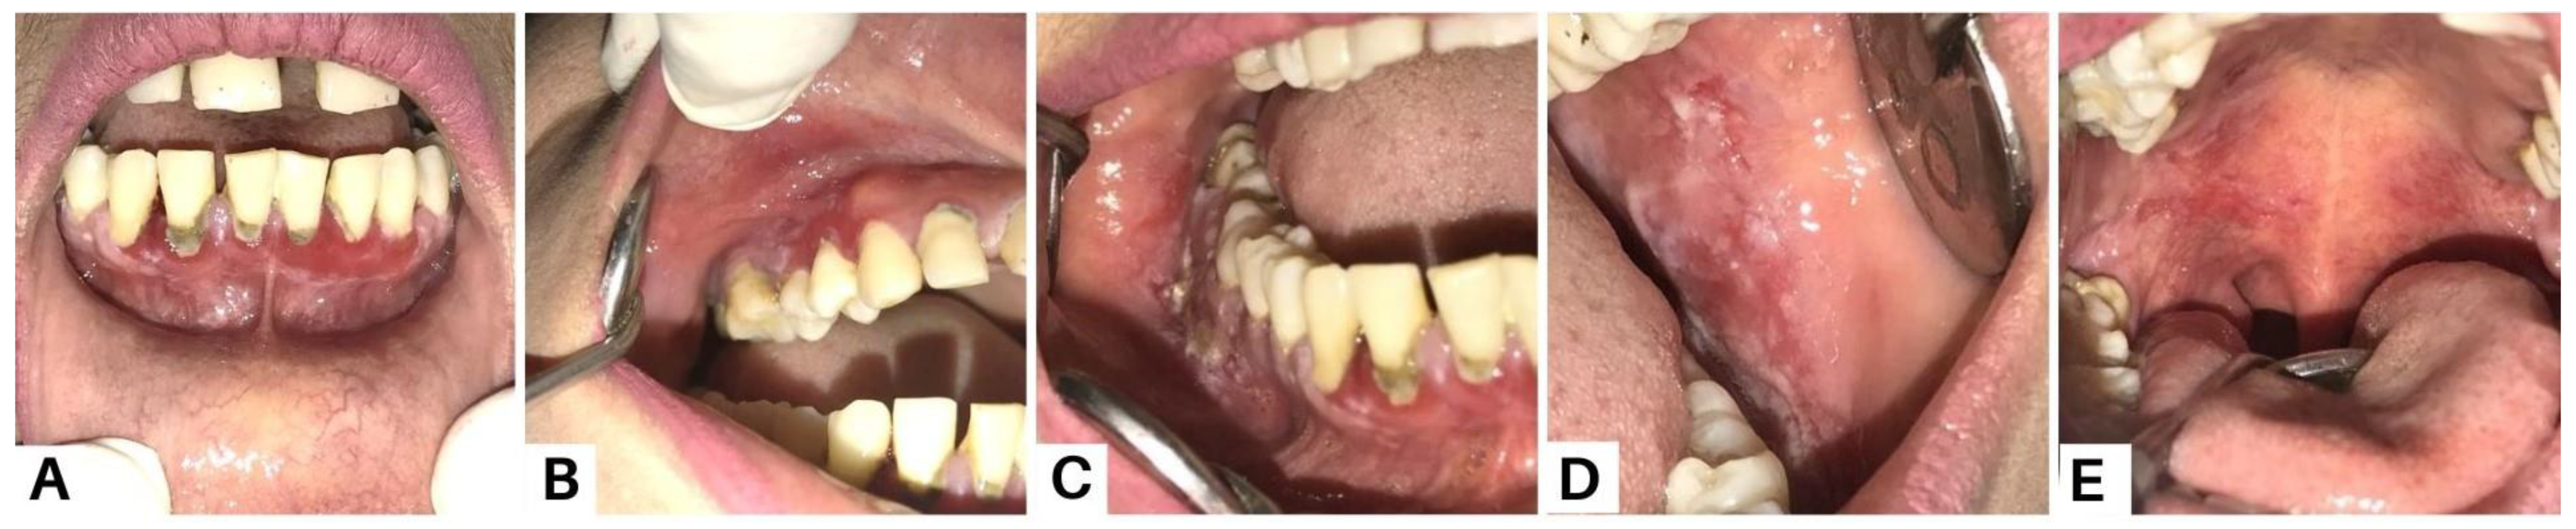

Figure 3.

Case 2, a 55-year-old man, complained of canker sores throughout his mouth starting four months prior. Symptoms were felt to be becoming worse and spreading to the lips, to the point where he was having difficulty eating and opening his mouth. There were no similar lesions on other parts of the body, and the patient had never had this complaint before. The figure shows the clinical presentation of case 2 on the first visit. Extra-oral examination revealed sanguinolenta crust lesions on the lips and commissure of the lips that bled easily (A); intra-oral examination showed multiple sloughed-over erosive lesions on almost the entire surface of the oral mucosa (B–H). PV is a rare but potentially life-threatening autoimmune disease affecting the mucosa and skin. PV frequently involves the mucocutaneous sites, resulting in superficial blistering and persistent ulcerative lesions [7,8,9]. Syphilitic pemphigus is an uncommon syphilitic variation that typically manifests as bullous lesions on the palms and soles [10,11]. Because of this variety of clinical symptoms, syphilis is recognized as a great imitator [10,12]. PV is distinguished by painful erosions and the blisters are rarely whole, presumably due to their fragility and brittleness. Buccal and palatine mucosa, lips, and gingiva are the most impacted sites. The erosions are multiple with various sizes and irregular forms, and they peripherally extend and frequently show delayed re-epithelialization. Gingival involvement largely presents as desquamative gingivitis [4]. Pemphigus pathogenesis involves an autoimmune attack against the desmosomes and hemidesmosomes responsible for epithelial cell adherence. Desmogleins are a type of desmosomal cadherin that are reactive to autoimmune antibodies in PV [9,13,14]. The binding of antibodies leads to acantholysis and the formation of blisters which tend to rupture easily, resulting in painful erosions that impair one’s quality of life and cause secondary infections with increased morbidity and mortality [14].